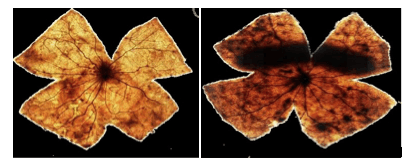

2002–2003 · Primeros estudios experimentales en retina

Modelo animal: ratas

Estudio transversal de un año de duración.

Exposición prolongada a luz blanca, luz azul y luz blanca exenta de azul, con y sin filtros selectivos.

Hallazgo clave:

Se observa daño retiniano significativo en los ojos expuestos sin protección a radiación cercana a 450 nm.

2003–2005 - Daño celular y mecanismos de muerte programada

Modelo animal: conejos

Estudio transversal y longitudinal de dos años de duración.

Exposición lumínica crónica en ciclos luz/oscuridad (12h/12h) a luz blanca y azul.

Implantación de lentes intraoculares con y sin filtro en cada ojo.

Hallazgo clave:

Las retinas sin protección activan mecanismos de muerte celular(genes pro-apoptóticos), mientras que las retinas fotoprotegidas activan mecanismos de supervivencia celular (genes anti-apoptóticos).

Estudios in vitro - Daño celular directo por LEDs

Modelo experimental: células de retina humana de donantes

Estudio transversal y longitudinal de un año de duración.

Exposición controlada a LEDs azules (longitud de onda corta), verdes (media), rojos (larga) y blancos (frío y cálido), en ciclos de luz/oscuridad de 12h/12h. Comparando condiciones con y sin fotoprotección.

Hallazgo clave:

La supervivencia celular aumentó de menos del 10% a más del 80% cuando se aplicó fotoprotección selectiva.